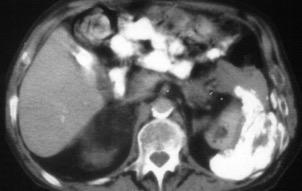

Absceso secundario a perforación de carcinoma. 3-4%. En flexura esplénica puede tener absceso subfrénico o empiema.

Empiema pleural secundario a carcinoma de la flexura esplénica (masa visible)

Lian R et al. Empyema caused by a colopleural fistula. Medicine (Baltimore) 2017/Osada T,, et al. Thoracic empyema associated with recurrent colon cancer: report of a case and review of the literature. Dis Colon Rectum 2001